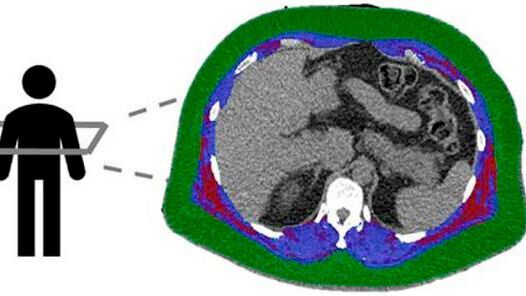

Researchers used CT scans to analyse each patient’s body composition, measuring the amounts and location of fat and muscle in a section of their torso.

All the patients were tested with cardiac positron emission tomography/computed tomography (PET/CT) scanning to assess how well their hearts were functioning. Researchers also used CT scans to analyse each patient’s body composition, measuring the amounts and location of fat and muscle in a section of their torso.